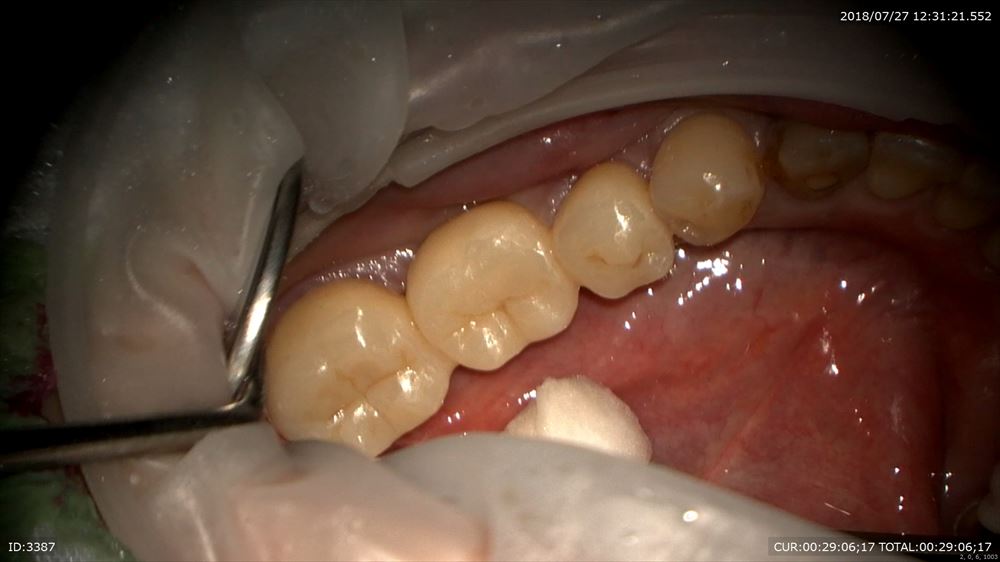

この様に仮歯で2ヶ月観察。問題なし。歯周病学会認定衛生士の歯周治療後私に昨日帰ってきました。

再発なしなので型とりへ

マイクロスコープを使用し準備

糸を入れるのは隙間を作るから。この緑を外すと

ここ。隙間ができここに型取りの材料を流します。

精密根管治療の予後は精密な型とりと精密な被せ物が重要だと報告があるようにこのステージが大切。